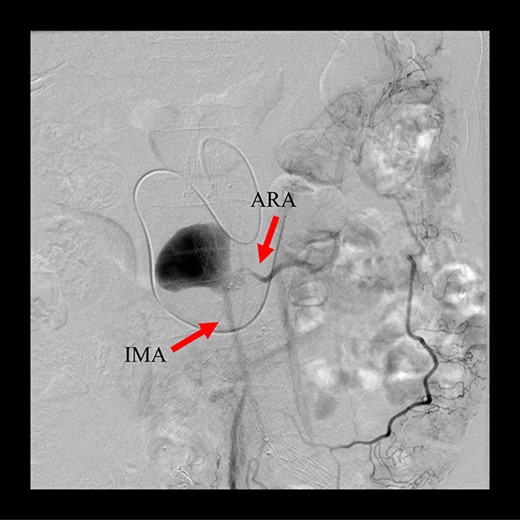

Angiography for decision-making revealed a type II endoleak from the IMA to the AAA, but no other visible endoleak (Fig. 2). Based on these findings, we planned additional EVAR for left CIAA, which was thought to have enlarged in natural course, and IMA embolization for the type II endoleak associated with sac enlargement. A staged strategy was devised. IMA embolization was planned several days after EVAR. Sac angiography from the IMA via Riolan’s arcade showed a flow-through endoleak to the ARA as a drainage artery (Fig. 3). Based on this finding, we embolized the ARA and the IMA with coils via Riolan’s arcade (Fig. 4). Selection and embolization of the drainage artery were technically feasible because of the flow from the IMA to the ARA. No deterioration of renal function due to ARA embolization was observed. One year after treatment, a CT scan demonstrated that the sac shrank to 42 mm with no evidence of a continuing endoleak (Fig. 5).

Sac angiography from the IMA via Riolan’s arcade showed a flow-through endoleak to the ARA as a drainage artery.